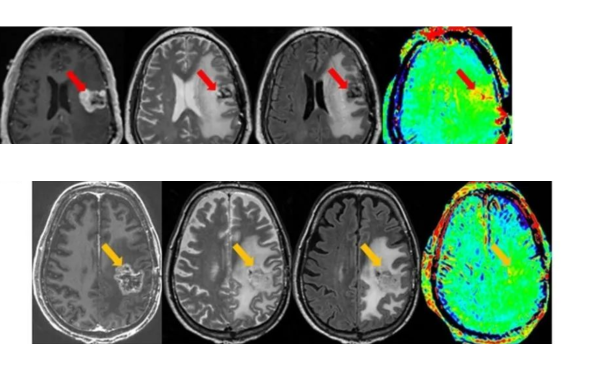

1.磁共振增强:放化疗后可导致血管内皮细胞损伤、坏死,造成血管内皮细胞紧密连接损害,BBB功能损害、通透性增强,在MR增强强化。MR增强上出现强化灶、新强化灶。类似肿瘤复发的影像学表现。胶质母细胞瘤放疗后,MR增强强化见于:70%:肿瘤复发、坏死(结节或多发强化区,术后3月后);30%:单侧放射性坏死(地图样强化)。

肿瘤复发:多发病灶沿白质纤维束播散、累及胼胝体

4.PWI灌注加权成像:可定量普股不同的脑血流动力学变量,如相对脑血容量rCBV等,rCBV是新生血管生成的影像学标志物。术后胶质瘤复发ASL和DSC的rCBV明显高于放射性坏死灶。